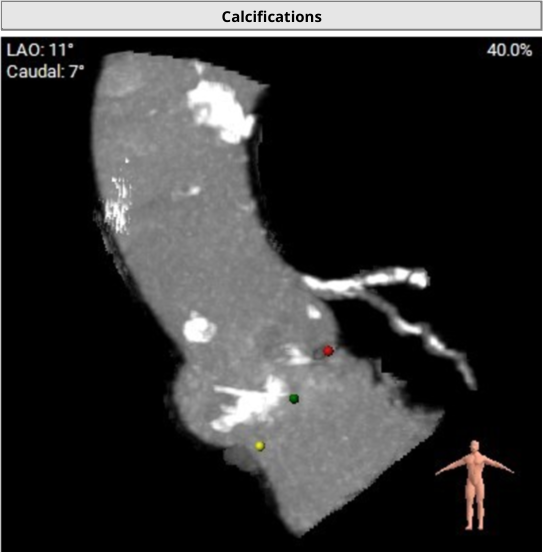

Calcification distribution

瓣叶增厚伴钙化,术前超声显示赘生物漂浮